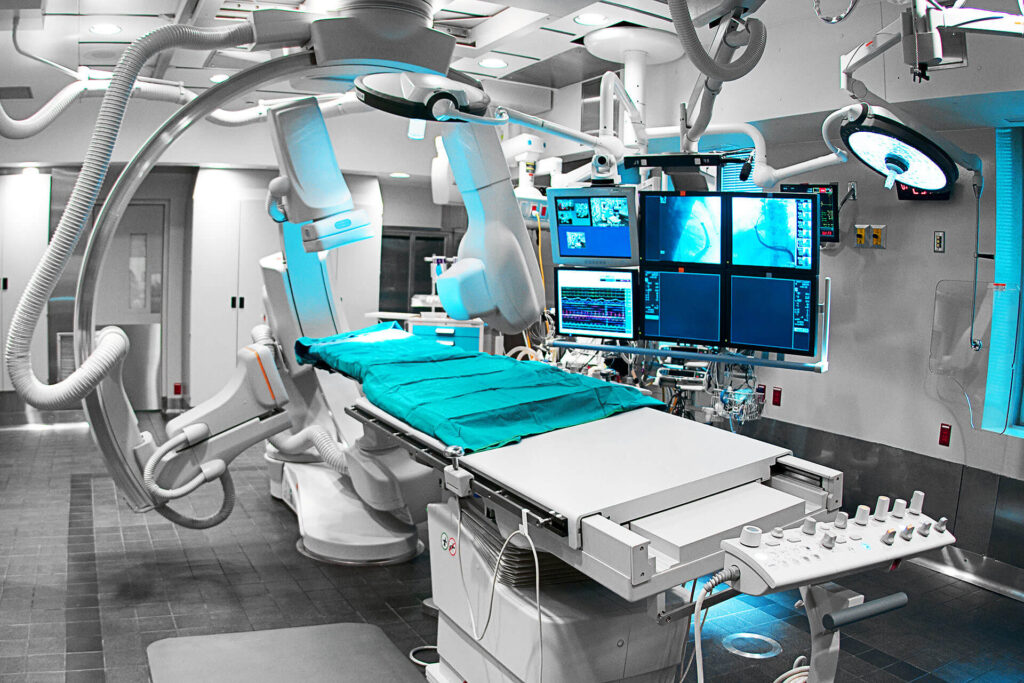

At Mildmay Hospital, our Surgical and Theatre Department is dedicated to restoring health, relieving pain, and improving quality of life. We are committed to the highest standards of surgical practice, guided by integrity, patient-centred care, and excellence. Our surgical and theatre services include:

Our theatres are fully equipped with modern surgical facilities, sterile techniques, and skilled professionals. We work closely with anaesthetists, surgeons, and nurses to ensure safety, comfort, and effective outcomes. Collaboration with other hospital departments ensures seamless care from diagnosis to surgery, recovery, and follow-up. Our surgeons, anaesthetists, theatre nurses, and support staff are highly trained, experienced, and committed to patient care. Their teamwork, professionalism, and compassion make every surgical journey safe and reassuring.